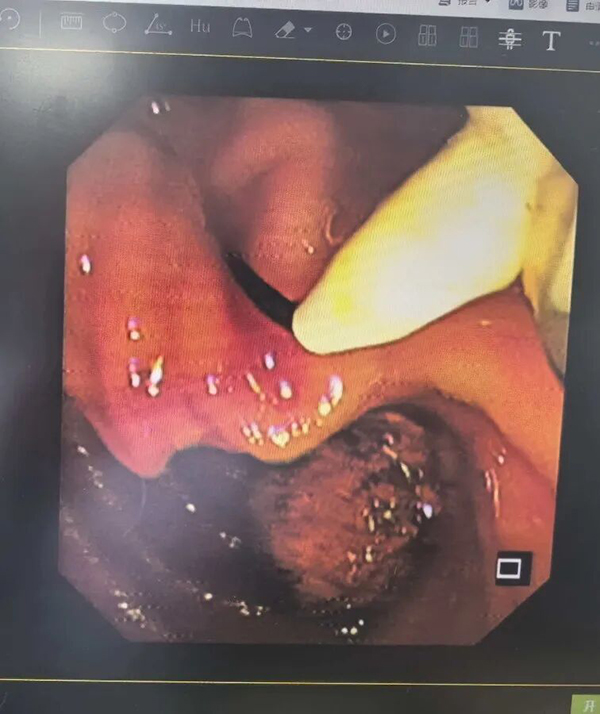

第一步:消化内科先行ERCP,解决胆总管结石。

入院后,消化内科团队为孙奶奶实施了ERCP(经内镜逆行胰胆管造影术),成功取出了胆总管结石,解除了胆道梗阻。

这一步为后续手术扫清了关键障碍,肝功能得到改善,感染风险下降,患者身体状态被调整到相对理想的水平。